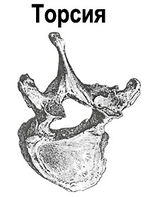

В тяжелых случаях искривление появляется и в других плоскостях: в сагитальной (вперед или назад) и в аксиальной (торсия или скручивание позвонков и их частей).[3]